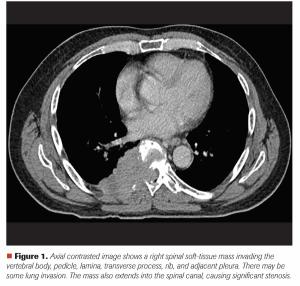

A 65-Year-Old Man With Back Pain and Imaging Findings of Spinal Cord Compression

ByMehmet Sitki Copur, MD,Scott Bell, MD, PhD, MPH,Paul Rodriguez, MD,Whitney Wedel, MD,Nicholas Lintel, MD,Thomas Zusag, MD,John L. Allen, MD Mehmet S. Copur, MD, and colleagues examine the case of a 65-year-old who presented with back pain and a large T8 spinal mass, leading to a diagnosis of multiple myeloma with spinal cord compromise.